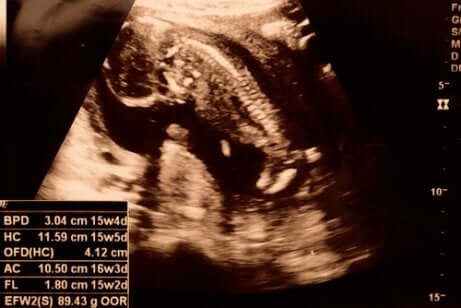

15. raskausviikko

Kun 15. raskausviikko koittaa, raskaus on kestänyt 14 viikosta ja 0 päivästä 14 viikkoon ja 6 päivään. 12 viikkoa vanha sikiö on tässä vaiheessa noin 8 senttimetrin pituinen ja 50 gramman painoinen.

15. raskausviikolla sikiön luuranko ei ole vielä kehittynyt, mutta sen selkäranka ja hermopäätteet ovat jo nähtävissä. Sen kädet ja jalat kasvavat, ja se pystyy jo taivuttamaan niveliään ja liikuttamaan käsiään. Kädet ovat jo lähes saavuttaneet lopullisen paikkansa, mutta jalat ovat edelleen suhteellisen lyhyet. Sikiön pää on edelleen vartaloon nähden suuri, mutta se pysyy jo pystyssä kaulan ja niskan avulla. Sikiö alkaa harjoitella imemistä, ja imemiseen tarvittavien lihasten kehittymisen myötä sen kasvot alkavat saada pyöreät piirteet. Vaikka sikiön silmät pysyvätkin edelleen kiinni, se pystyy jo aistimaan valon.

Sikiön keuhkot kehittyvät edelleen, ja se alkaa hengittää sisään ja ulos pieniä määriä lapsivettä. Tämä on erittäin tärkeää keuhkojen kehittymisen kannalta. Sikiö pystyy myös jo maistamaan erilaisia makuja lapsivedessä. Se alkaa totutella ensimmäisiin makuihin nimenomaan juomalla lapsivettä, jonka makuun äidin syömä ruoka vaikuttaa. Tässä vaiheessa raskautta sikiön sydän pumppaa noin 28 litraa verta joka päivä.